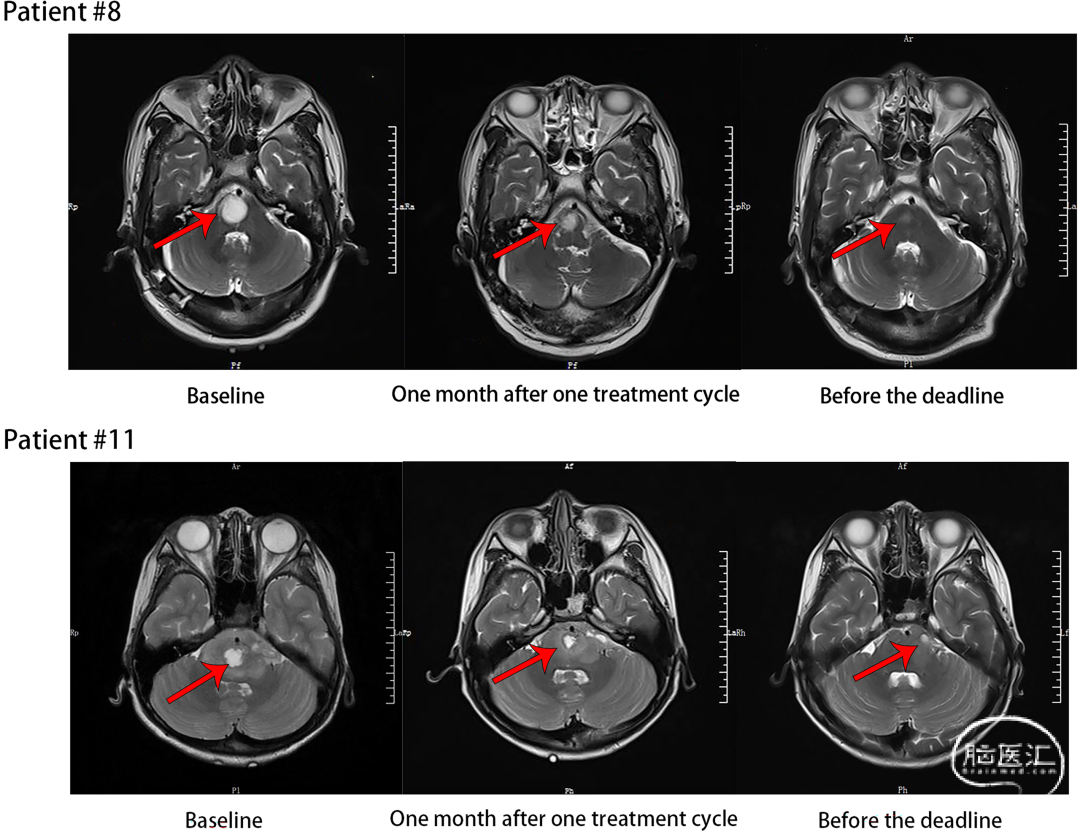

这项发表于《International Journal of Cancer》的研究,首次在全球探索了声动力疗法联合放疗用于脑干胶质瘤(含高级别)的安全性。核心结论:非常安全。所有11名患者治疗相关的不良反应均为1-2级(轻度至中度),未出现任何3级及以上严重不良反应或剂量限制性毒性。治疗耐受性良好。疗效信号:在可评估的患者中,72.7%的患者病情保持稳定,18.2%达到部分缓解(肿瘤缩小)。研究通过MRI影像直观地展现了肿瘤治疗后的变化。例如,患者#8和患者#11在基线期、治疗周期结束后1个月以及随访截止前的MRI对比显示,肿瘤得到了有效控制或缩小。

图3. 上图展示了两位患者治疗前后MRI的对比变化。患者的中位无进展生存期(PFS)达到 9.2个月,中位总生存期(OS)为 11.7个月,为后续研究奠定了坚实的基础。